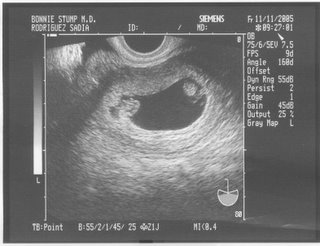

I was 7 weeks pregnant when I had my first ultrasound. The doctor pointed out the shared outer sac (chorion) and the two distinct inner sacs (amnions).

Once we’d called everyone we needed to share the good news with, I hit Google, and quickly concluded from their monochorionic/diamniotic (mono/di) state that my little ones had split from a single cluster of identical cells somewhere between 3 and 9 days after conception. I’ll tell you how I made the calculation in a little bit.

• At six weeks, the baby's heart is starting to develop into a structure more similar to its final form, rather than the tube that it starts out as. If you have an ultrasound at this time, you might even detect a very rapid little heartbeat that is working almost twice as fast as yours.

• Your baby’s eyes and nose will start showing slightly on ultrasounds, and you’ll be able to see where the ears will form.